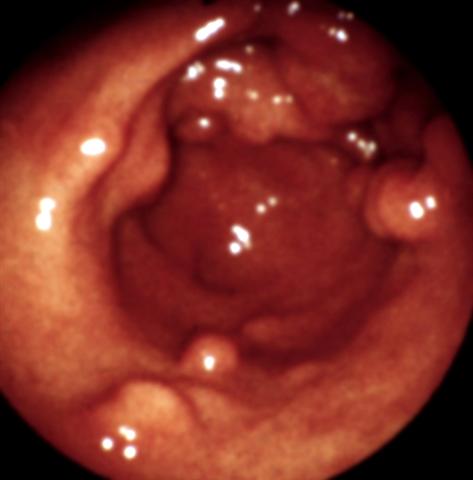

Рис. 12. Эндоскопическая картина желудка в норме и при различных заболеваниях. Полипоз желудка: видны множественные полипы на широком основании.